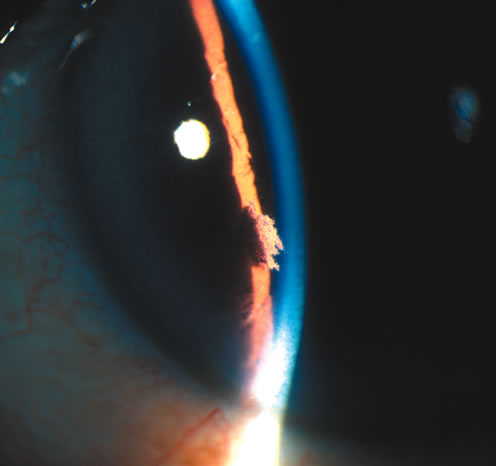

SURGICAL

One of the more common reasons for focal iris atrophy in recent years is found in eyes that have undergone extracapsular cataract extraction with placement of an intraocular lens implant.45,47 This is an erosion phenomenon that occurs with anterior chamber lens and sulcus fixated lens (Fig. 7).48,49 Iris atrophy is also seen commonly around surgical or laser iridectomies.

Fig. 7. Iris atrophy with transillumination defects (arrow) after extracapsular cataract surgery with a sulcus fixated intraocular lens. (© University of Illinois at Chicago.)